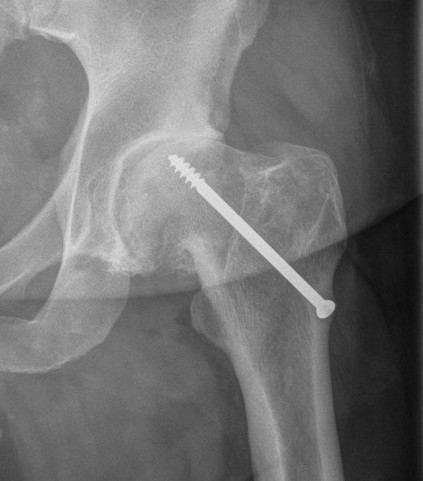

AVN

OA post SCFE AVN post SCFE